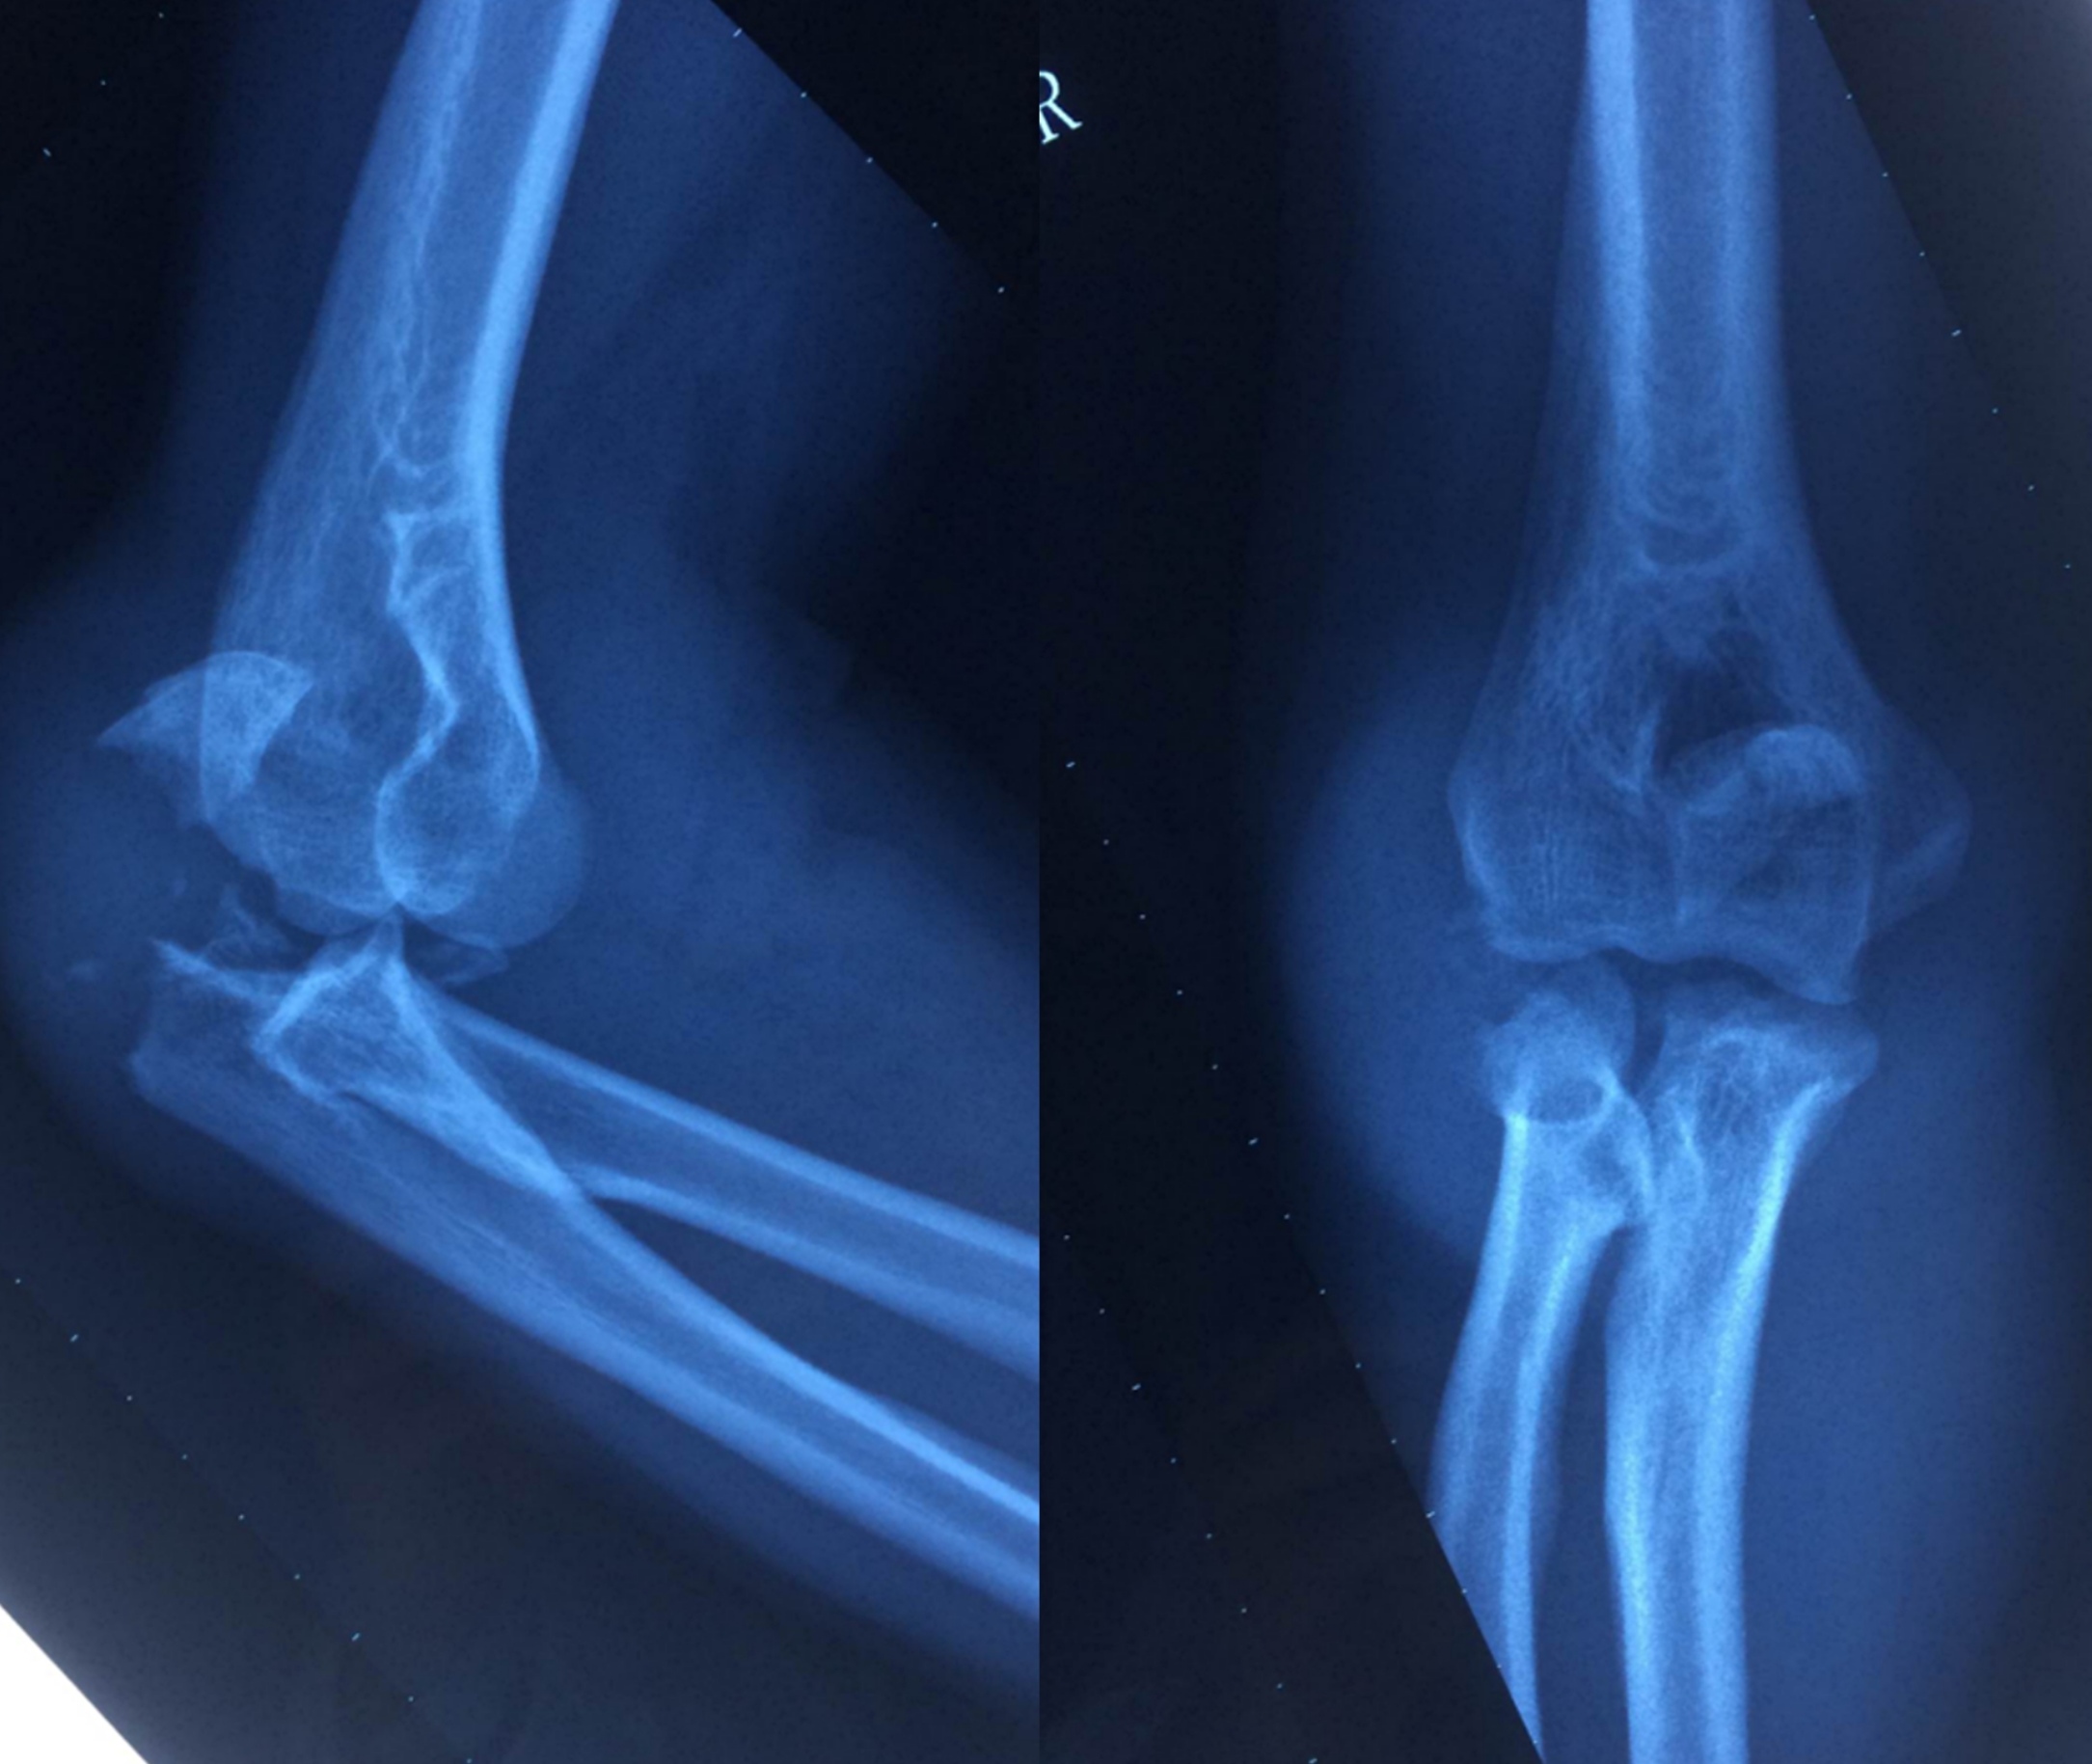

郑金龙主任表示将此病例诊断为经鹰嘴骨折肘关节后脱位,是由于患者具有以下几个特点:鹰嘴骨折且伴有冠突骨折,桡骨小头部分骨折,整个肘关节是后脱位,肱桡关节和肱尺关节都是破坏不稳定的。在治疗上选择了肘关节后入路,一个切口可以处理三个骨折部位,手术顺序先采用张力带固定处理冠状突骨折,再用解剖板固定桡骨小头骨折,用锚钉修复外侧副韧带,最后处理尺骨鹰嘴的粉碎性骨折。

患者术后四个月恢复良好,肘关节基本上达到正常的伸曲角度。

1591340303369577.jpg

▲患者术后影像资料